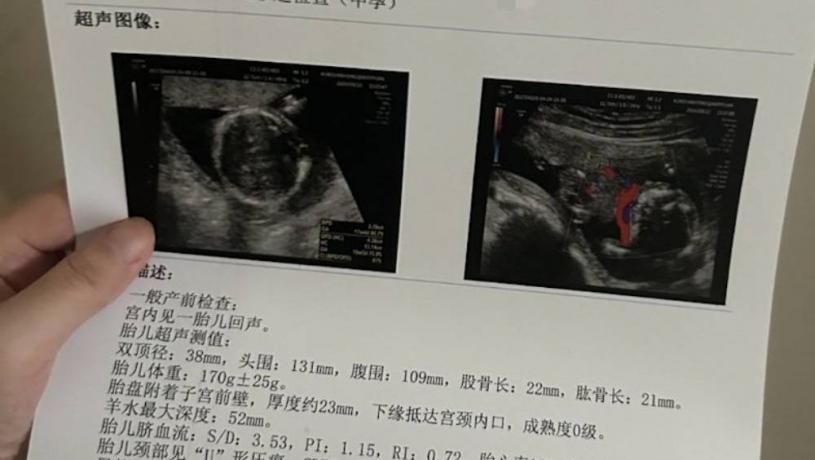

9 u% o$ ^5 j E C% b. g! ]5.39.217.77小溪的相關產檢報告。 微博

她告訴澎湃新聞,代孕機構事先承諾的代孕補償是24萬元,分階段支付。她被安排到私立醫療機構產檢,第一個月在昆山某門診部產檢,後來轉到某醫院。據她回憶,產檢時,其他代孕媽媽用別人的身份證掛號,小溪用自己的身份證,但是做產檢的醫療機構都沒有給她建檔。在懷孕5個多月後,11月6日小溪意外流產,11日接受清宮手術,接下來就如上述給人趕走了。 |